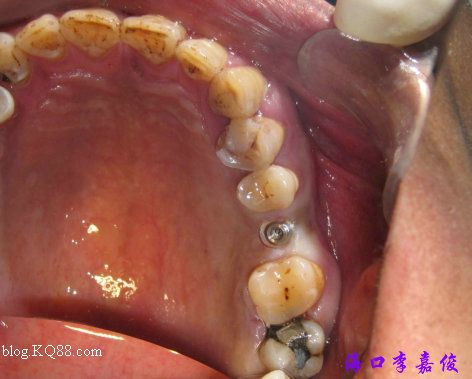

環(huán)切定位

36種植窩成形后要植入4.8X13mm植體